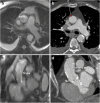

Transcatheter Aortic Valve Implantation (TAVI) is increasingly being used in patients with severe aortic stenosis who are not candidates for surgery. ECG-gated CT angiography (CTA) plays an important role in the preoperative planning for these devices. As the number of patients undergoing these procedures increases, a subset of patients is being recognized who have contraindications to iodinated contrast medium, either due to a prior severe allergic type reaction or poor renal function. Another subgroup of patients with low flow and low gradient aortic stenosis is being recognized that are usually assessed for severity of aortic stenosis by stress echocardiography. There are contraindications to stress echocardiography and some of these patients may not be able to undergo this test. Non-contrast MRI can be a useful emerging modality for evaluating these patients. In this article, we discuss the emerging indications of non-contrast MRI in preoperative assessment for TAVI and describe the commonly used MRI sequences. A comparison of the most important measurements obtained for TAVI assessment on CTA and MRI from same subjects is included. Teaching Points • MRI can be used for preoperative assessment of aortic annulus. • MRI is an alternate to CTA when iodinated contrast is contraindicated. • Measurements obtained by non-contrast MRI are similar to contrast enhanced CTA. • MRI can be used to assess severity of aortic stenosis.